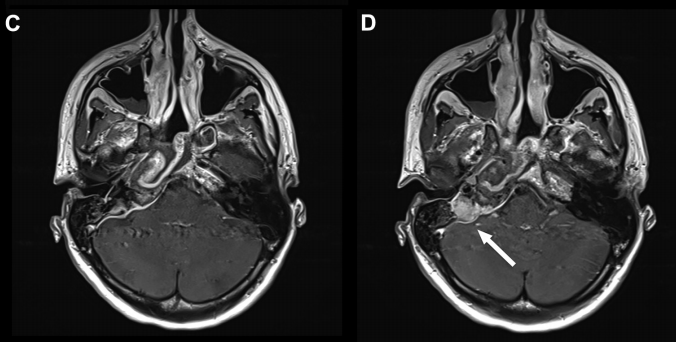

增强 MRI 显示病灶在岩尖、耳蜗和内听道侧面和后部出现均匀强化病灶, T2 低信号和 T1 高信号,病灶导致右侧内听道 ICA 和海绵窦向前移位。

- 手术成功地切除了囊肿的绝大部分(次全切除,指切除了绝大部分肿瘤,通常指90%以上)。

- 术后扫描显示鼻中隔瓣修复良好。

- 影像也显示,在岩尖区域难以到达的一个小角落,还残留了一小部分囊肿。这是为了最大程度保护周围极其重要的神经和血管结构而做的谨慎选择。